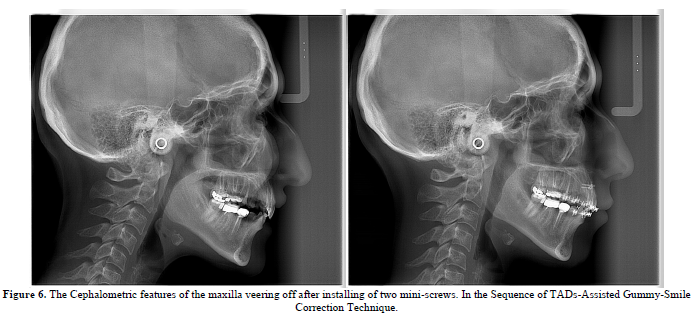

The technique in essence depends on installing two mini-screws in basal position to create a counter-clockwise movement of the maxillary arch as to counteract the causes of the gummy smile itself.

In other word, to create an intrusion Moment on the Anterior Portion of the Maxillary Arch what mollify the appearance of the exposed tissues when smiling in Gummy-Smile Patients (Figure 3).

Hitherto, the cephalometric and clinical outcomes support the aforementioned approach (Figure 6).